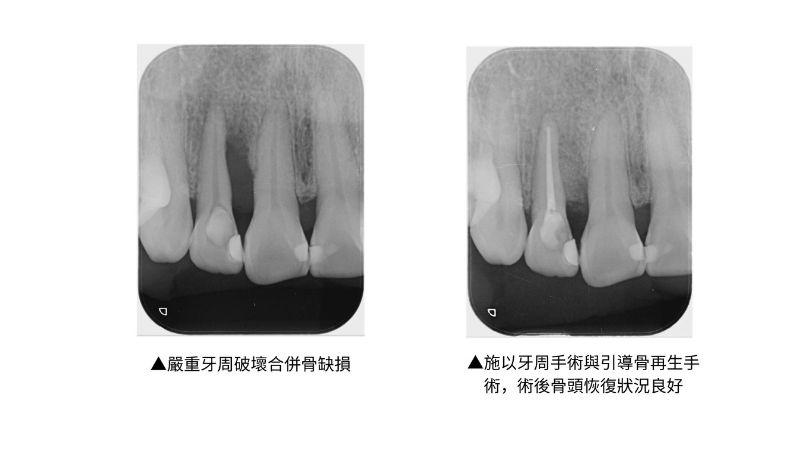

牙周病治療後最重要的一環為術後口腔清潔衛生維護,每三至六個月的定期回診檢查與洗牙,倘若有復發的跡象,可以經由早期發現而早期治療。方能確保牙周病病情受到穩定控制,爾後,全口重建治療與植牙治療成功率便會提高,欲接受植牙的患者倘若出現齒槽骨缺陷時,醫師會利用引導骨再生之技術與骨修整手術等治療,除了能夠同時達到齒槽骨整形與修補改善外,還可以大大增加植牙成功機會。